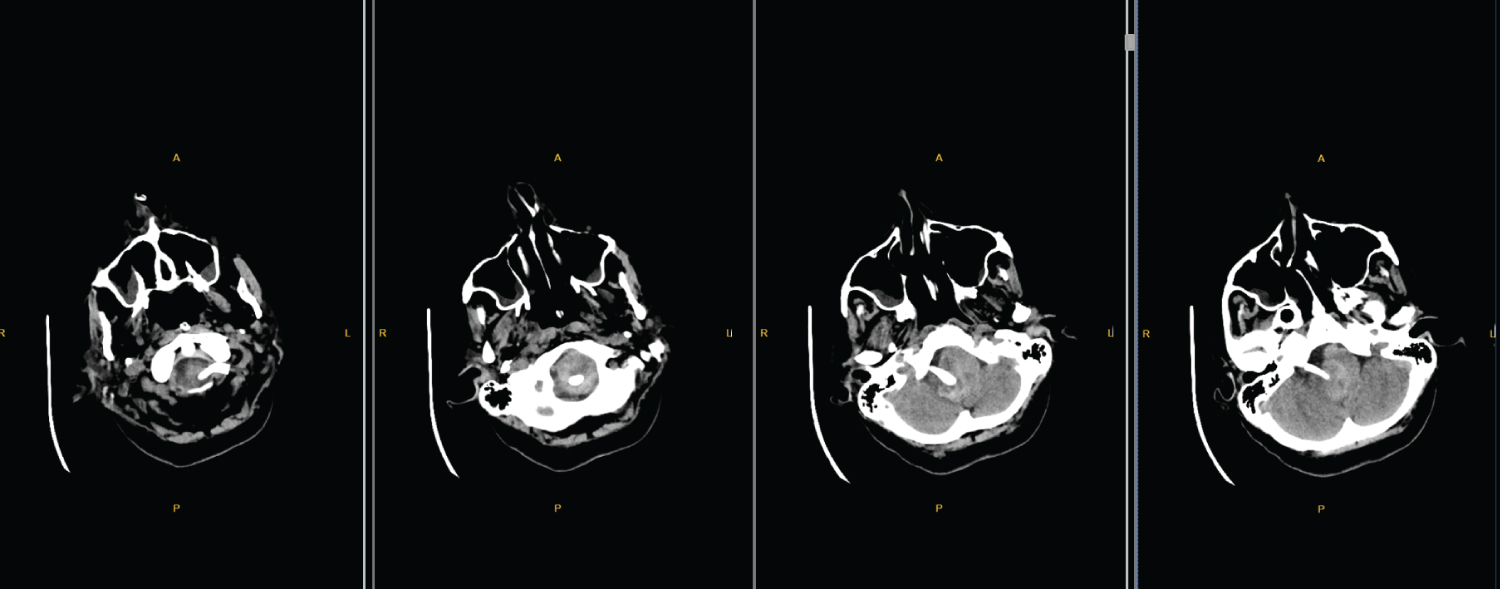

The patient was a 47 year old female admitted to Ankara Bilkent City Hospital (Ankara, Turkey) in June 2018, who had been experiencing symptoms of cough, dyspnea and hoarseness for 1 year. Her cough was treated with several antibiotics and diagnosed with bronchiectasis but there was no improvement of her complaints. In June 2019 because of the progression of her dyspnea, admitted to our hospital's emergency service. Her tachypnea got worse and saturation fell down. At last, the patient has elective intubation in the E.R. On the elective intubation, E.R doctor noticed that the patient's left vocal cord was paralyzed and an emergent head and cervical computer tomography angiography performed. Ct scans revealed a large vertebrobasilar aneurysm and obvious compression of the brainstem (Figure 1). Patient transferred to a neurosurgery intensive care unit and started antibiotic of teicoplanin with the loading dose of 400 mg 2 × 1 and continued 400 mg 1 × 1.

Figure 1: Ct scans revealed a large vertebrobasilar aneurysm and obvious compression of the brainstem. View Figure 1